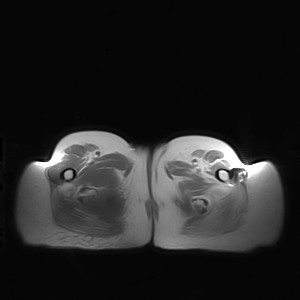

标题: MRI2691:读片病例2

我帮传的没看到病史!!!

图像太差了 1、右侧臀肌旁脓肿? 建议增强 2、左侧股骨头坏死并半脱位

1、左侧股骨头坏死并髋关节半脱位;

2、右侧臀肌感染,(可能褥疮所致)